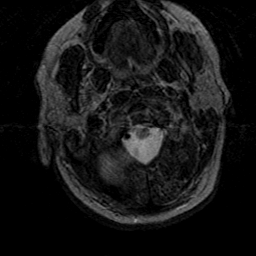

Subacute Stroke, overlay -- Slice #0

[Home][Help][Clinical] Slice 0

Click on sagittal image to select slice. Click on thin tickmark to change timepoint, or thick tickmark for overlay.